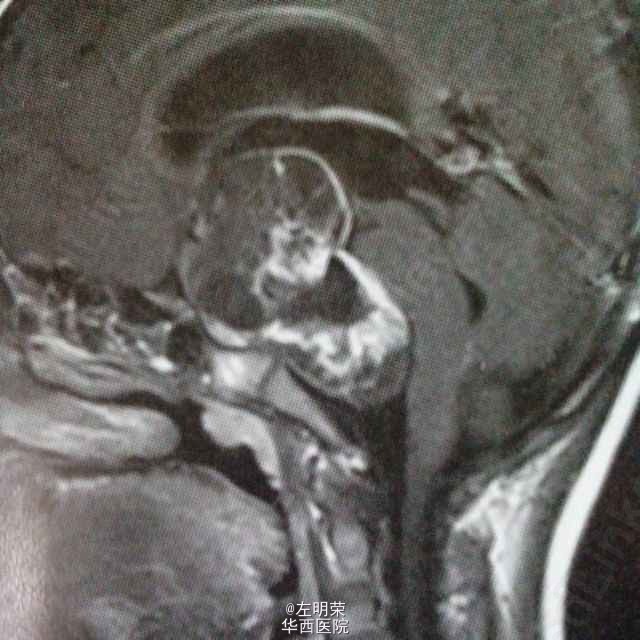

女,6岁,以间断头痛3个月余,加重2个月之主诉入院。MRI示:桥前池-鞍上池-三脑室内巨大不规则均匀强化影,鞍背骨质可见破坏,病灶内可见囊变坏死区。可见脑干及病灶周围实质明显受压移位,病灶与脑实质分界清楚;考虑诊断脊索瘤,颅咽管瘤,神经鞘瘤。术中见肿瘤囊实性,血供丰富,边界尚清,位于鞍背上方,脑干前方,与基底动脉,大脑后动脉粘连紧密,给予全部切除;病理示:神经鞘瘤。